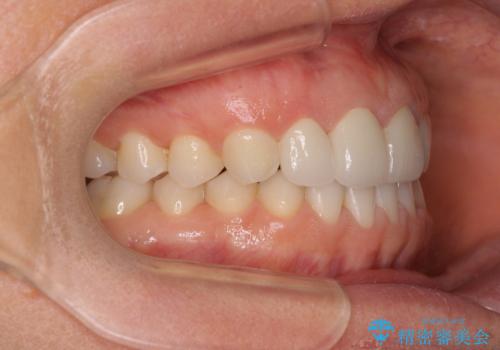

矯正治療後は、仮歯とした上顎前歯をオールセラミッククラウンにて補綴治療を行うこととしました。

日本と海外を拠点に仕事をされていらっしゃるため、数ヶ月治療があいてしまうことがあり、期間はかかりましたが、2年間で望み通りの前歯に仕上げることができました。